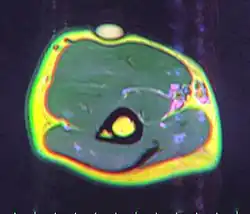

A physical exam is typically the easiest way to diagnose it. Rarely, a tissue biopsy or imaging may be required. The imaging modality of choice is magnetic resonance imaging (MRI) because it has superior sensitivity of distinguishing it from liposarcoma as well as mapping the surrounding anatomy.[22]

MRI showing lipoma of the arm -